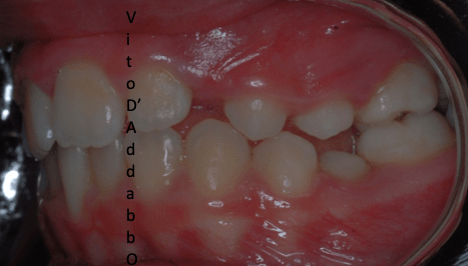

dopo – fase 2